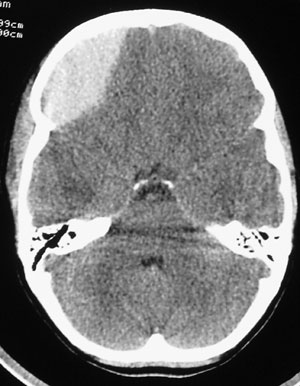

CT chest exams of 120 trauma patients were used in the study. Measurements were taken at both sites and compared. Interestingly, the authors stratified patients into 4 BMI categories then analyzed the data based on these groupings.

DESIGN: Patients were separated into body mass index (BMI) quartiles, with BMI calculated as weight in kilograms divided by height in meters squared. From each BMI quartile, 30 patients were randomly chosen for inclusion in the study on the basis of a priori power analysis (n = 120). Chest wall thickness on computed tomography at the second ICS in the MCL was compared with the fifth ICS in the AAL on both the right and left sides through all BMI quartiles.

PATIENTS: Injured patients aged 16 years or older evaluated from January 1, 2009, to January 1, 2010, undergoing computed tomography of the chest.

RESULTS: A total of 680 patients met the study inclusion criteria (81.5% were male and mean age was 41 years [range, 16-97 years]). Of the injuries sustained, 13.2% were penetrating, mean (SD) Injury Severity Score was 15.5 (10.3), and mean BMI was 27.9 (5.9) (range, 15.4-60.7). The mean difference in chest wall thickness between the second ICS at the MCL and the fifth ICS at the AAL was 12.9 mm (95% CI, 11.0-14.8; P < .001) on the right and 13.4 mm (95% CI, 11.4-15.3; P < .001) on the left. There was a stepwise increase in chest wall thickness across all BMI quartiles at each location of measurement. There was a significant difference in chest wall thickness between the second ICS at the MCL and the fifth ICS at the AAL in all quartiles on both the right and the left. The percentage of patients with chest wall thickness greater than the standard 5-cm decompression needle was 42.5% at the second ICS in the MCL and only 16.7% at the fifth ICS in the AAL.